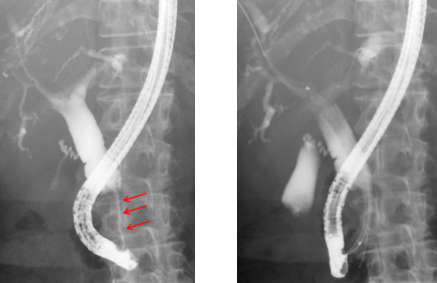

内視鏡による金属ステント留置術

(左図) 癌による胆管狭窄、黄疸の患者さんに対して行ったERCPの画像。矢印の部分の胆管が糸のように細くなっており、それより上流の胆管は正常よりも太く拡張しています。

(右図) 内視鏡を用いて胆管狭窄の部位に金属ステントを留置しました。これにより胆汁の流れが改善し、この患者さんは黄疸から回復しました。血液検査でも肝酵素は正常値まで低下し、その後の治療を安全に行うことができました。